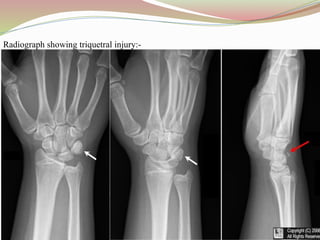

Radiograph showing triquetral injury:-